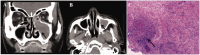

The relationship between antineutrophil cytoplasmic antibody (ANCA)-associated vasculitis (AAV) and lung cancer remains unclear. A 66-year-old man presented with pulmonary nodules. Histological examination of a specimen from computed tomography-guided percutaneous transthoracic biopsy revealed adenocarcinoma. The patient was treated using cryoablation and systemic chemotherapy. Sixteen months later, the patient presented with fever, nasal inflammation, recurrent lung lesions, elevated serum creatinine levels, and high levels of ANCA. Histological examination of a specimen from ultrasound-guided percutaneous renal biopsy revealed pauci-immune necrotizing crescentic glomerulonephritis. The patient responded to treatment, but granulomatosis with polyangiitis recurred and he later died. This case highlights the possibility of sequential AAV with lung cancer. Although this is relatively rare, further research is needed to better understand the association or pathophysiological link between lung cancer and AAV.